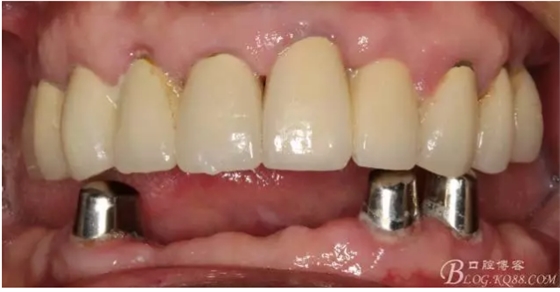

修復(fù)后照片,

患者的口腔衛(wèi)生保持的不好,有大量的軟垢附著,

最近復(fù)查的照片,牙周維護(hù)好一些了,畢竟是一個80歲的老爺爺了,每次來拄著拐,還要跟著很多人攙扶著過來很不容易了。